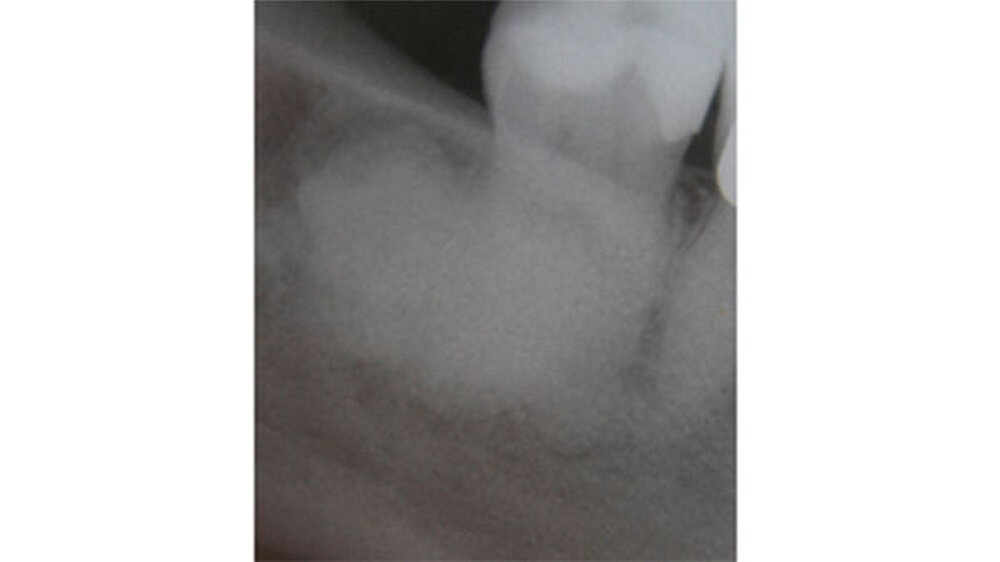

Eine 65-jährige beschwerdefreie Patientin stellte sich zur Routineuntersuchung in unserer Praxis vor. Diagnostiziert wurde eine generalisiert moderate, lokalisiert schwere chronische Parodontitis. Die im Rahmen der parodontalen Vorbehandlung durchgeführte Röntgendiagnostik zeigte eine haselnussgroße wolkige Verschattung regio 48. Anamnestisch wurde eine operative Entfernung des Weißheitszahns 48 vor ungefähr 35 Jahren angegeben.

Der Zahn 47 reagierte positiv auf den Vitalitäts-/ Sensibilitätstest. Eine dreidimensionale Bildgebung musste von der Patientin aus wirtschaftlichen Gründen abgelehnt werden. Die Verdachtsdiagnose: ein Osteom oder ein Zementom. Zur explorativen Probeexzision wurde nach minimalinvasiver Schnittführung ein Knochendeckel präpariert, was eine berührungslose Darstellung der knöchernen Veränderung erlaubte. Weil die Veränderung sehr hart und spröde war, konnte sie nicht in toto entfernt werden.